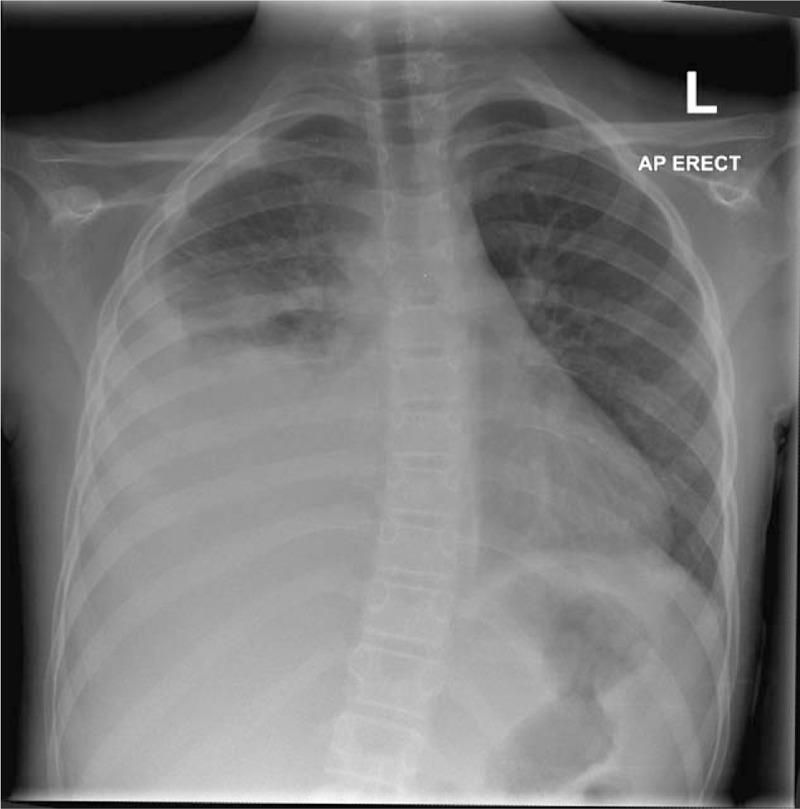

We describe the unique case of a child with pneumonia presenting with acute scoliosis and abdominal pain, without any typical features of the disease.A 10-year-old girl presented to the emergency department on 3 consecutive days with right-sided abdominal pain. There were no associated features, in particular, no fevers or respiratory symptoms. On the first 2 presentations, observation,examination, and blood test findings were unremarkable. Chest x-ray and abdominal ultrasound were also normal. On the third presentation a marked scoliosis was noted and abdominal examination revealed right-sided tenderness with rebound. The patient was admitted and a computed tomographic scan of the abdomen arranged. Unexpectedly, this revealed a right lower lobe pneumonia and associated pleural effusion. Despite treatment, the parapneumonic effusion enlarged rapidly and she developed respiratory distress, necessitating transfer to a tertiary centre.The diagnosis of pneumonia can be challenging because of a lack of respiratory signs, the masking of systemic features by antipyretic effects of first-line analgesics, and a high rate of false-negative chest radiographs. The development of acute scoliosis should lead the clinician to strongly consider pneumonia in such circumstances.

我们描述了一例独特的病例,一名患有肺炎的儿童出现急性脊柱侧弯和腹痛,无该疾病的任何典型特征。一名10岁女孩连续三天因右侧腹痛到急诊科就诊。无相关特征,特别是无发热或呼吸道症状。在前两次就诊时,观察、检查及血液检查结果均无异常。胸部X光和腹部超声也均正常。第三次就诊时发现明显的脊柱侧弯,腹部检查显示右侧有压痛及反跳痛。患者入院并安排了腹部计算机断层扫描。出乎意料的是,扫描显示右下叶肺炎及相关胸腔积液。尽管进行了治疗,肺炎旁积液仍迅速增大,她出现了呼吸窘迫,因此需要转至三级医疗中心。由于缺乏呼吸道体征、一线镇痛药的退热作用掩盖了全身特征以及胸部X光片假阴性率高,肺炎的诊断可能具有挑战性。在这种情况下,急性脊柱侧弯的出现应促使临床医生高度怀疑肺炎。